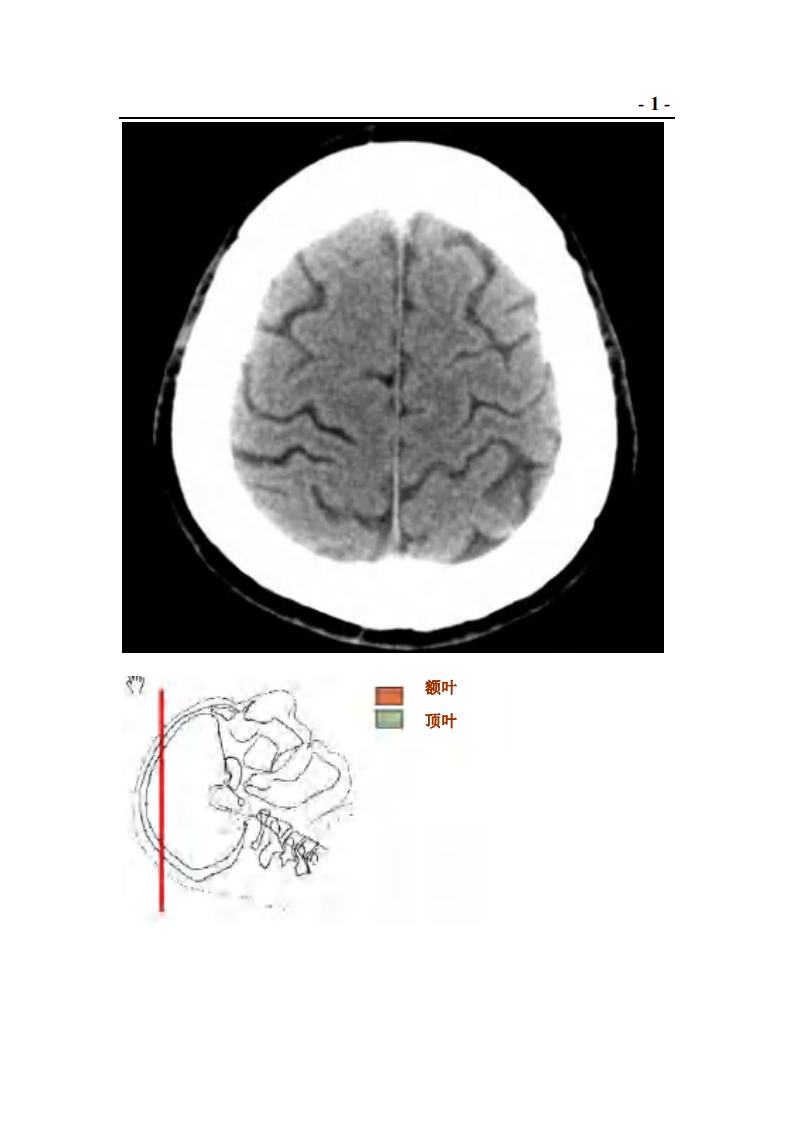

神经外科CT与MRI头颈部.pdf